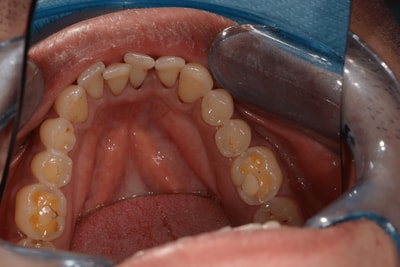

Situation Initiale

Etude du cas et proposition